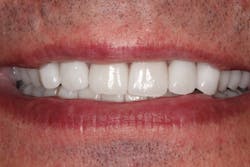

Figure 4: Provisionals

Figure 5: Provisionals

Figure 6: Provisionals

A periodontist completed the crown lengthening surgeries in three separate visits. After healing, the teeth were prepared for crowns, and provisionals (figures 4–6) were placed.

Chris “test drove” the provisionals for function and esthetics. He returned to my office after a few days to give his approval for the final steps. None of the temporary crowns had come off, which is a sign that the final result will be long-lasting.